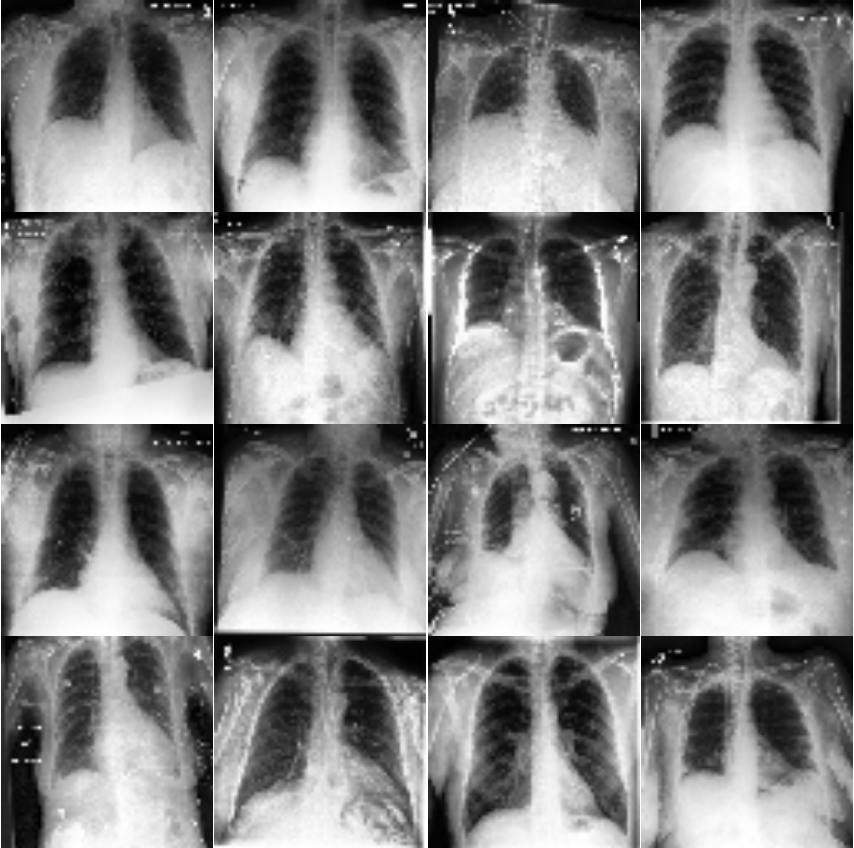

| Panel A | Panel B |

|---|---|

|

|

From observation of Figure 4, it is visible for humans that the chest areas are clear in the healthy chest X-ray images. However, the images for COVID cases are not quite clear. This is an indication that there are inflammatory cells or other related body fluids filled in the chests. Instead of air which shows up on the pictures to be clear area, these areas in COVID cases tend to be cloudy and unclear.

This section presents visualization of the proposed architecture. These visualizations are presented in Figure 5. Unlike Figure 2 that is an executive summary with each position representing many samples, these visualizations in Figure 5 are sample-wise plots. In other words, the 10 original images that are sized 128 by 128 in Panel A and Panel B are the same samples in the second row, 1st Conv. Layer, and the third row, 2nd Conv. Layer.

Visualization Interpretation The plot in Figure 5 of the original images for COVID-19 patients has grey and cloudy textures in chest area. Because an X-ray picture is at its brightest when most of the light beams emitted are bounced back from the object, we can observe bones to be the color “white” while the margin to be completely “black”. For muscle and organs inside human body, X-ray beams that are emitted can only partially be collected and this causes the greyscale on the X-ray images in chest area. For COVID-19 patients, there are grey and shaded area in the chest X-ray pictures. This is due to the inflammatory fluid when patients exhibit pneumonia-like symptoms. The fluid inside chest area is a consequence of human immune system fighting against outside diseases. This shaded (as seen in Panel A of Figure 5) prevents us from observing the clear location of lungs. This is different in Panel B where the lung areas are dark and almost black, because a healthy lung is filled with air (i.e. normal cases and X-ray image presents color black). The black and white contrast in the two panels is directly related to how much inflammatory fluid there is in human lungs. This contrast translates to greyscale on pictures and it is directly related with COVID cases and non-COVID cases (i.e. response variable ). The same contrast can be seen using the new variables (these are ’s based on equation 4) in the 1st Conv. Layer (sized 61 by 61). For COVID-19 patients, the lung area is cloudy and unclear while the healthy cases it is clearly visible. This is not a surprising coincidence because the proposed new variable modules, ’s, are engineered using equation 4 which relies on the response variable in training set. The images sized 61 by 61 from the proposed algorithm is a direct translation of not only the original pixels but also response variable. In other words, this visualization presents how I-score sees image data.

| Panel A: | Panel B | |

| True Label: COVID | True Label: Non-COVID | |

| Input Images: 128 by 128 | Input Images: 128 by 128 | |

| (Randomly select 10 samples) | (Randomly select 10 samples) | |

| Row (a) |  |

|

Discussion for Figure 5.

This figure presents visualization summary for 10 randomly sampled images from COVID class and non-COVID class (each has 10). Panel A is for COVID patients and Panel B is non-COVID people. The first row plots the original images that are sized 128 by 128. The 1st Conv. Layer generates new variables. We plot the same 10 images from both classes using these 3,721 variables in the second row. We also print the predicted COVID probabilities on top left corner of each image. The 2nd Conv. Layer generate variables. We plot the same 10 image samples from both classes using these 900 variables in the third row. We also print the predicted COVID probabilities on top left corner of each image assuming using only these 900 variables as predictors. The plot of the original images for COVID-19 patients has grey and cloudy textures in chest area. This is due to inflammatory fluid when patients exhibit pneumonia-like symptoms. This shaded (as seen in Panel A) prevents us from observing the clear location of lungs. This is different in Panel B where the lung areas are dark and almost black which means the lung is filled with air (i.e. normal cases). The black white contrast in the two panels is directly related to how much inflammatory fluid there is in human lungs which translate to greyscale on pictures. The same contrast can be seen using the new variables (these are ’s based on equation 4) in the 1st Conv. Layer (sized 61 by 61). For COVID-19 patients, the lung area is cloudy and unclear while the healthy cases it is clearly visible.

|

Discussion for Figure 5.

Original Images to 1st Conv. Layer. The input images are sized 128 by 128. With the 1st Conv. Layer constructed, we have new variables. We trace back to the same samples as shown in the first row of Figure 5 and use these 3,721 variables only. When we plot these samples with these new variables, we resize them back in matrix form of 61 by 61. Panel A is for COVID class and Panel B is for non-COVID class. In addition, we use Model 1 in Table 4 to produce the texts that states predicted probability of COVID class. The red color implies ground truth to be COVID class (Panel A) and the green color implies ground truth to be non-COVID class (Panel B).

1st Conv. Layer. to 2nd Conv. Layer. From the resulting matrix of the 1st Conv. Layer, we are left with 3,721 variables. We go through the proposed design in Table 4 and we create a new convolutional layer, i.e. 2nd Conv. Layer. This new layer has variables. We take the same 10 sampled images from before and we use these 900 variables to present these images. In this presentation, we resize these 900 variables into shape 30 by 30. In other words, we get a smaller matrix that we can plot that exhibit mini version of similar patterns as before. We use Model 4 to generated the predicted probabilities. These probabilities are printed on the top left corner of each image and they are color coded similarly as before (red probabilities have ground truth of COVID class while green probabilities have ground truth of non-COVID class).